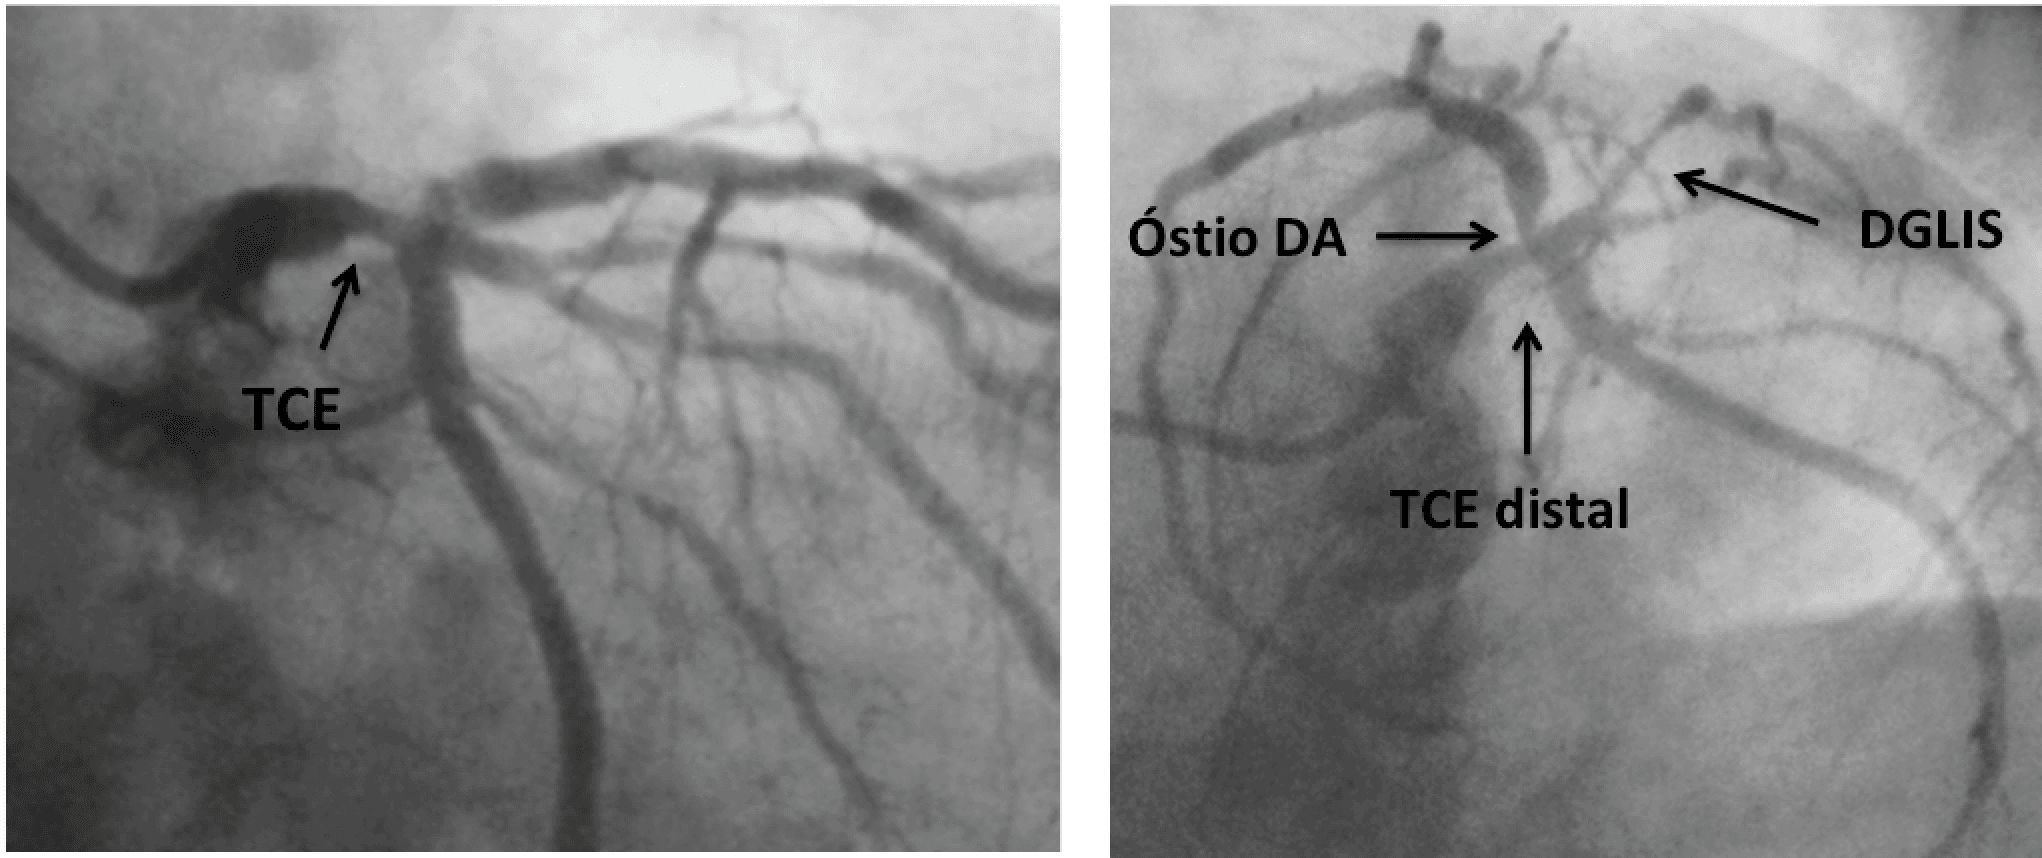

Nos últimos 2 anos, desde a publicação dos resultados de 5 anos do estudo EXCEL, que comparou angioplastia com stent farmacológico (ICP) versus cirurgia de revascularização do miocárdio (RM) em casos …

Nos anos 70 e 80, estudos randomizados que incluíram aproximadamente 200 pacientes com lesão de tronco da coronária esquerda (TCE) mostraram que a revascularização cirúrgica era superior ao tratamento…